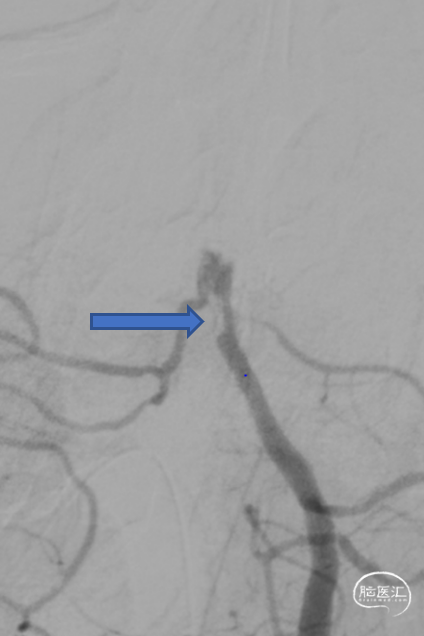

微导丝微导管通过闭塞段,在右侧大脑后动脉手推造影证实真腔,明确闭塞段,可见造影剂返流至基底动脉尖部,且证明闭塞确为支架内再狭窄导致闭塞。

释放加奇4.0mm*30mm Syphonet®取栓支架,可见支架通体显影。